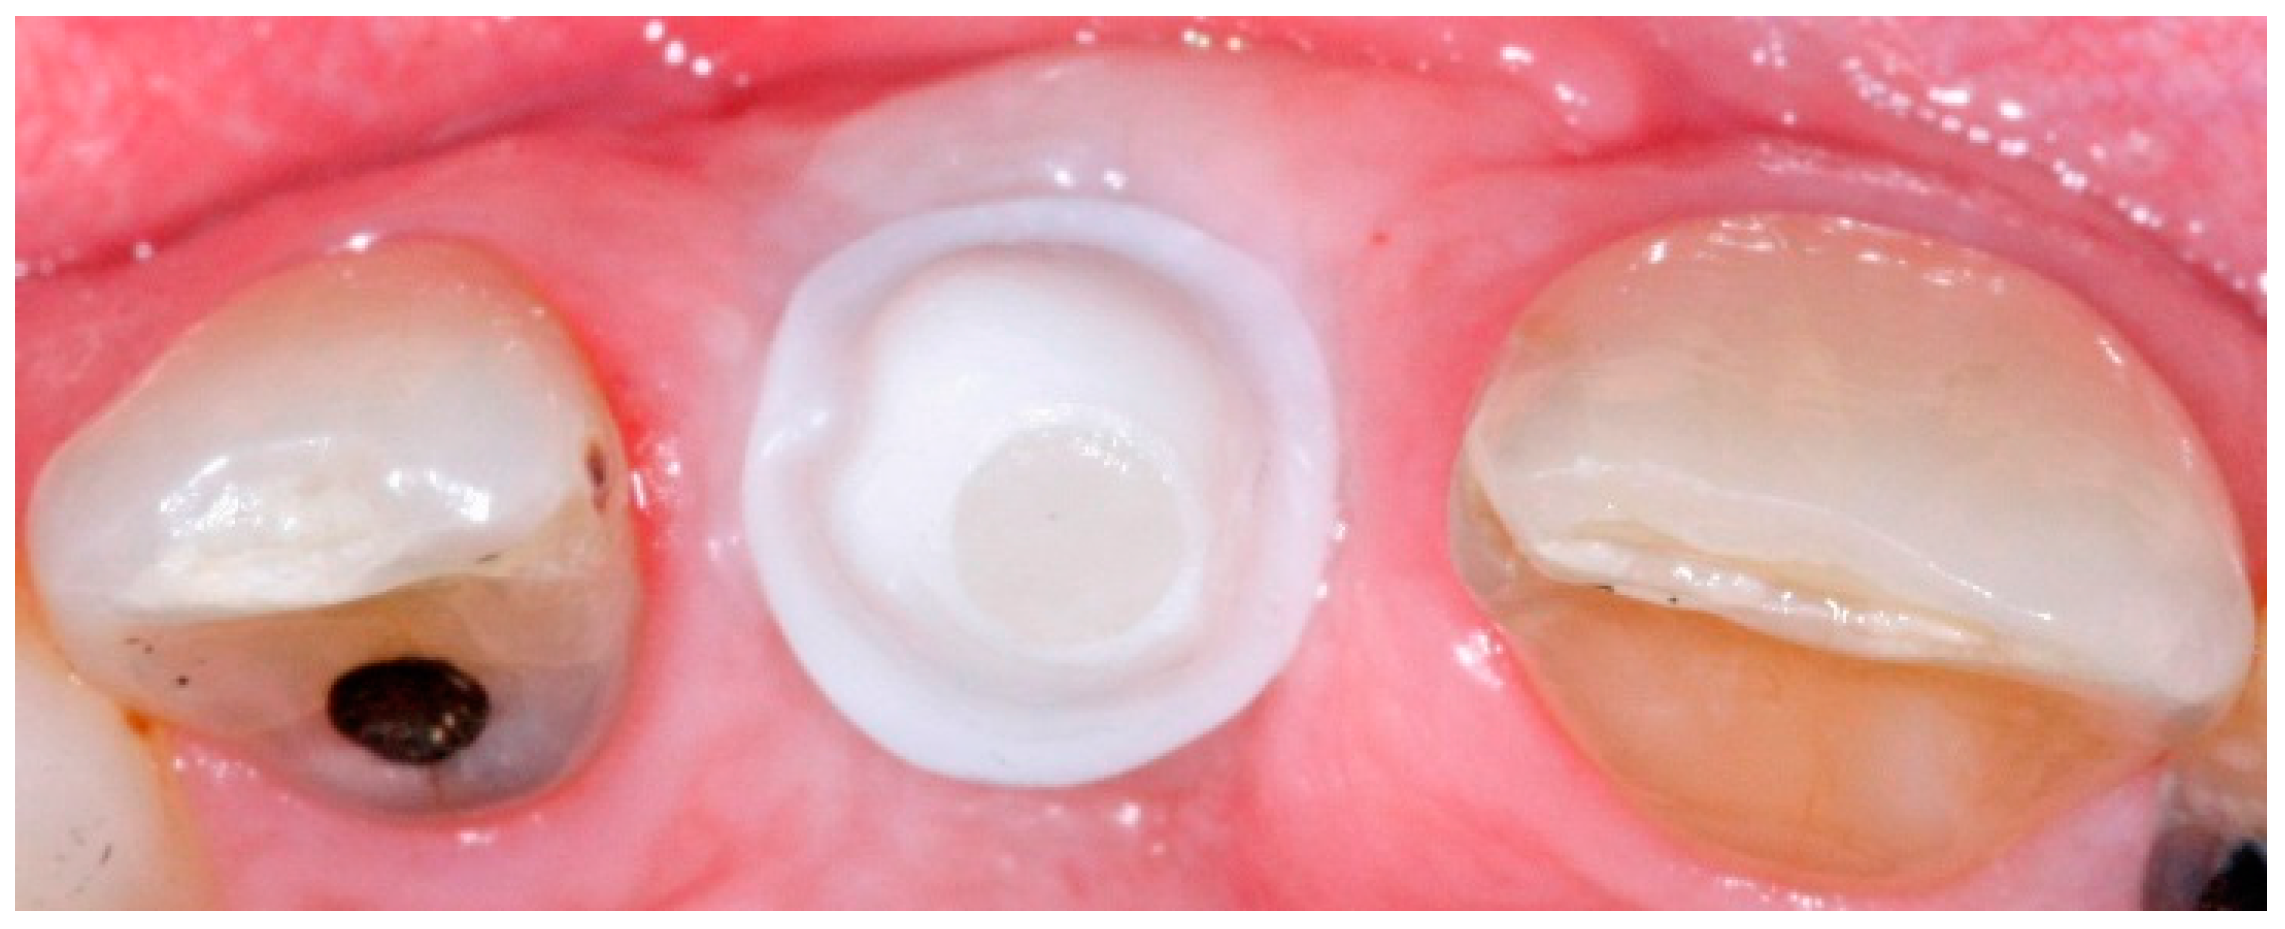

Sealing Socket Abutment a novel digitalized strategy for immediate Dental Abutment Impression these include abutment level impressions, indirect (closed tray) and the direct (open tray) techniques for implant level impressions and splinted. initially, the final abutment is inserted onto the dental implant (fig. abutment level impression is a method of taking an impression by connecting the abutments to the top of the implant fixture. the aim of a. Dental Abutment Impression.